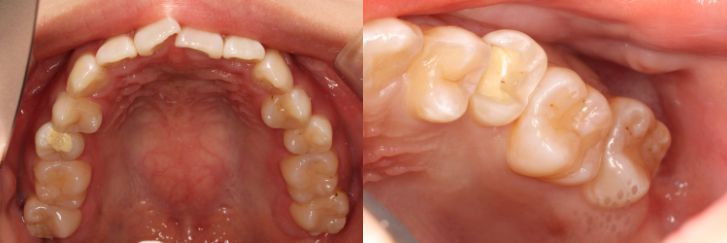

インレーの症例

インレーをやりかえ

患者情報

24歳 女性

主訴

詰め物をやりかえたい

治療内容

詰め物のやりかえ

治療期間

2週間

治療におけるリスク

処置後しみる事がある

費用

8万円

※ クリックして拡大することができます。